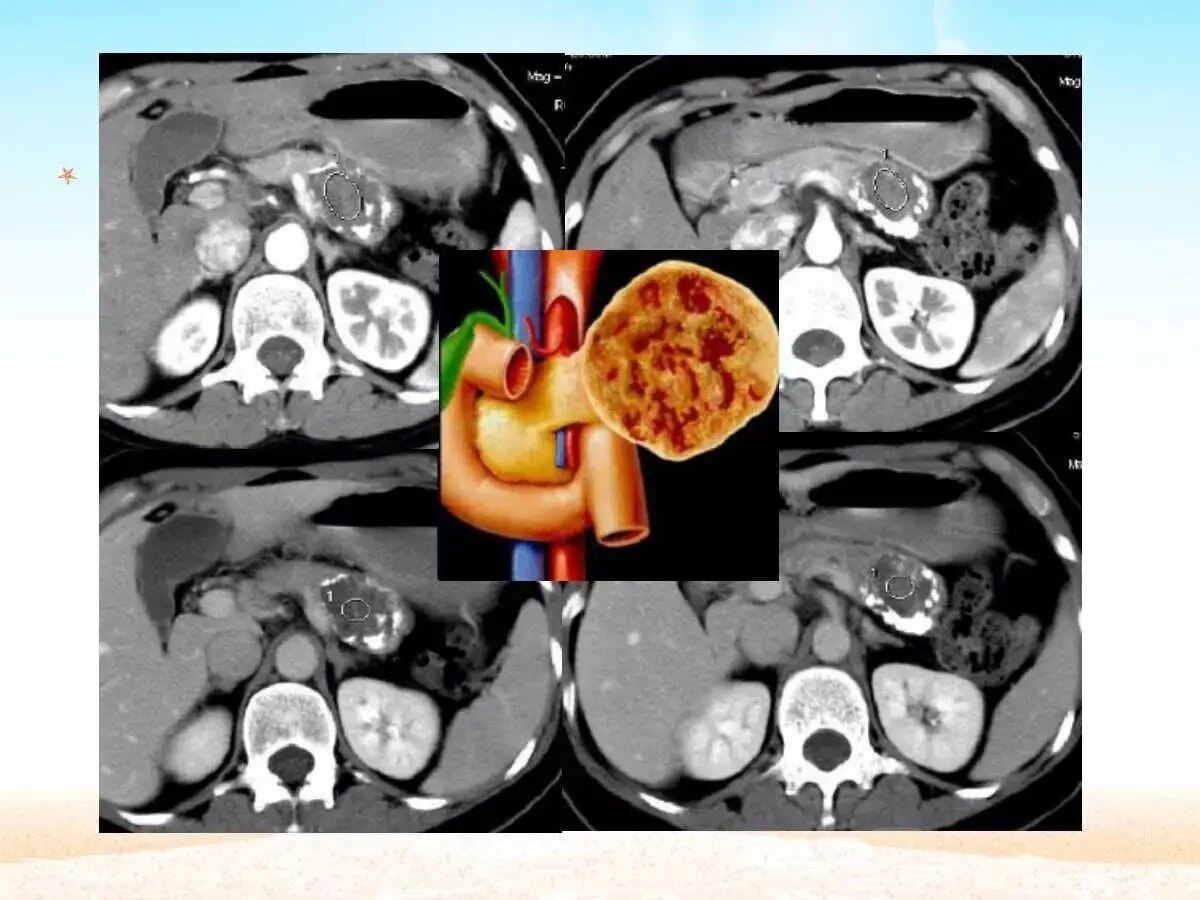

胰腺浆液性囊腺瘤(serouscysticneoplasm,SCN)约占原发性胰腺囊性肿瘤的16%[1],主要好发于中老年女性,且女性发病年龄普遍早于男性,也称为“奶奶瘤”,与胰管不相通[2]。SCN可发生于胰腺的任何位置,其中胰体和胰尾部发生率较高,且有逐年增加的趋势[2-3]。胰腺SCN常见的临床表现为非特异性腹痛,其他症状包括胰胆管梗阻、腹部肿块、乏力、恶心呕吐和体重减轻等,亦有相当比例的患者无症状,为影像学检查偶然发现[2,4]。SCN绝大多数为良性病变,预后良好,极少发生侵袭和转移,死亡率接近0%[5]。临床上对于SCN患者通常选择定期观察随访,只有临床症状明显、病灶较大、生长迅速或无法排除恶性可能的SCN才考虑手术切除[5-6]。SCN是一种预后良好的胰腺良性肿瘤,无症状患者通常无需采取手术治疗[4]。随着医学影像辅助检查的发展,胰腺囊性病变的检出率日益增加[12],因此提高术前影像诊断准确率,规避手术的创伤与风险变得日益重要。在临床实践中,常因SCN影像学表现不典型而无法排除其他具有恶变潜能的肿瘤,如MCN、IPMN、pNET等。CT和MRI是诊断胰腺囊性病变最常用的影像检查方法,PET-CT、EUS、超声造影、EUS-FNA也对诊断具有辅助价值。微囊型是SCN最常见与典型的影像学形态表现[2,14],纤维瘢痕、中央钙化和周围血管改变是诊断SCN的特异性CT征象,有助于与MCN、IPMN的鉴别诊断[15]。但SCN在CT中表现多样,部分病例缺乏钙化、纤维瘢痕等典型特征,而部分则可能出现类圆形、单囊型外观,或有分隔增厚、胰管扩张、胰腺实质萎缩等不典型表现,可能是术前误诊的重要原因[1]。(文献来源:王端,吴东,戴梦华,等.胰腺浆液性囊腺瘤手术切除患者172例的临床及影像学特征分析.中华胰腺病杂志,2024,24(01):33-38.DOI:10.3760/cma.j.cn115667-20230930-00036)浆液性囊腺瘤是良性肿瘤,常见于60岁以上的女性,恶变率极低,整体恶变率低于1%[18,19]。肿瘤生长过程中会压迫邻近器官,有时为了控制症状仍需要切除,尤其是年轻患者;如肿瘤最大径>10cm,建议手术切除,因为患者生存期长,肿瘤生长过程中可能会产生压迫症状或与血管致密粘连包裹,导致肿瘤不可切除。大部分浆液性囊腺瘤生长缓慢且无症状,所以如能获得明确诊断,不需要定期随访。(文献来源:楼文晖.对胰腺囊性肿瘤诊治中几个问题的思考[J].中华外科杂志,2024,62(10):909-912.)SCN是一种良性肿瘤,其特征是成簇的微小囊肿,这些囊肿的隔膜含有丰富的血管。恶性肿瘤的风险极低[9]。然而,对于大小超过4cm的肿瘤或因可能出现恶性肿瘤或症状表现(如腹痛、饱胀和黄疸)而快速生长的肿瘤,建议切除[10,11]。SCN偶尔会长得非常大,并与周围组织形成严重的炎症粘连,使手术作和解剖复杂化[12]。SCN的特点是恶性潜能极低[9]。对于肿瘤超过4cm、表现出可疑的恶性肿瘤特征、表现出快速生长(每年>4mm)或引起症状,可考虑手术切除[10,11]。巨大的SCN会诱发严重的炎症和粘连,压迫多个周围器官和组织,从而使手术干预复杂化。在某些情况下,切除邻近器官和主要血管(如结肠和门静脉)对于切除大SCN是必要的[12,17\u201219]。Liu等[12]报道了6例巨型SCN手术病例。在一个例子中,胰十二指肠切除术由于门静脉广泛受累而导致切除不完全,需要术中修复。另一例病例需要部分切除横结肠,因为肿瘤粘连牢固[12]。此外,巨型SCN通常会形成大量动脉供血器,导致脆弱的静脉结构扩张并使胰腺切除术复杂化。本病例中的肿瘤有两条原发性供血动脉:部分栓塞的GDA和完全栓塞的DPA。这种方法有效地防止了肿瘤扩张,缩小了扩大的引流静脉的大小,便于手术治疗。事实证明,进入肿瘤背侧的DPA栓塞至关重要,因为该区域最初难以进入。此外,在SMA线上方横切胰腺并将肿瘤从脾静脉向胰头分离,尽管门静脉分支晚期受伤,但仍可以安全、完全切除。考虑到胰十二指肠切除术对此类高血管分布肿瘤的复杂性,术前栓塞是巨型SCN的有效管理策略之一。高血管性胰腺肿瘤的术前动脉栓塞术可能会控制术中大量出血的风险,从而可能促进良好的术后病程。鉴于肿瘤难以管理、广泛的血管分布和严重的炎症粘连,巨型SCN的胰十二指肠切除术可能具有挑战性。采用IR进行术前流入控制是大型高血管性胰腺肿瘤有价值的胰腺切除术策略之一。(文献来源:MatsuyoshiT,IkenagaN,NakataK,OkamotoD,MatsumotoT,AbeT,WatanabeY,IdenoN,KakuK,FujimoriN,OhuchidaK,OkabeY,OdaY,IshigamiK,NakamuraM.Acaseofpreoperativeembolizationforagianthypervascularpancreaticserouscysticneoplasminpancreaticoduodenectomy.SurgCaseRep.2024Sep6;10(1):208.)